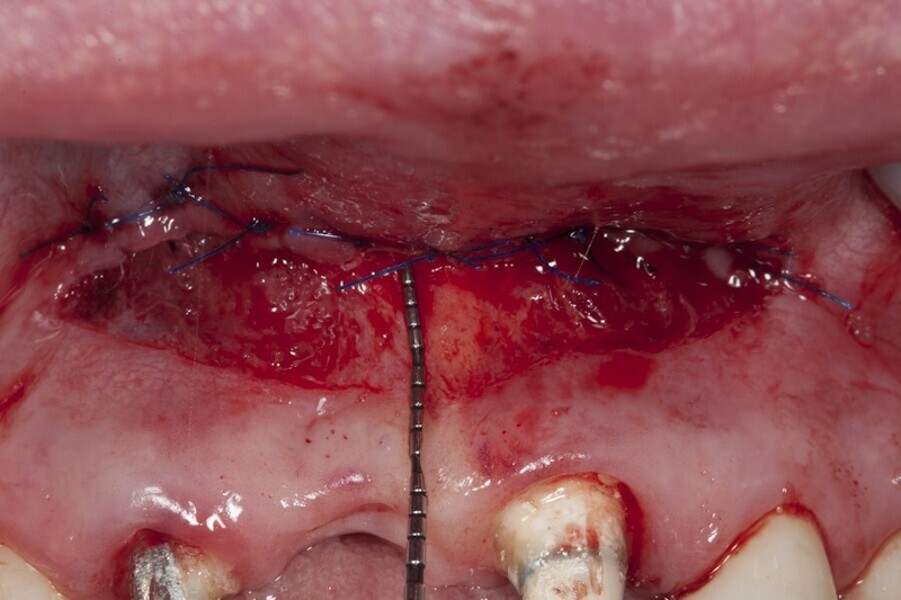

Biomodulacja laserem Nd:YAG z użyciem głowicy Genova®